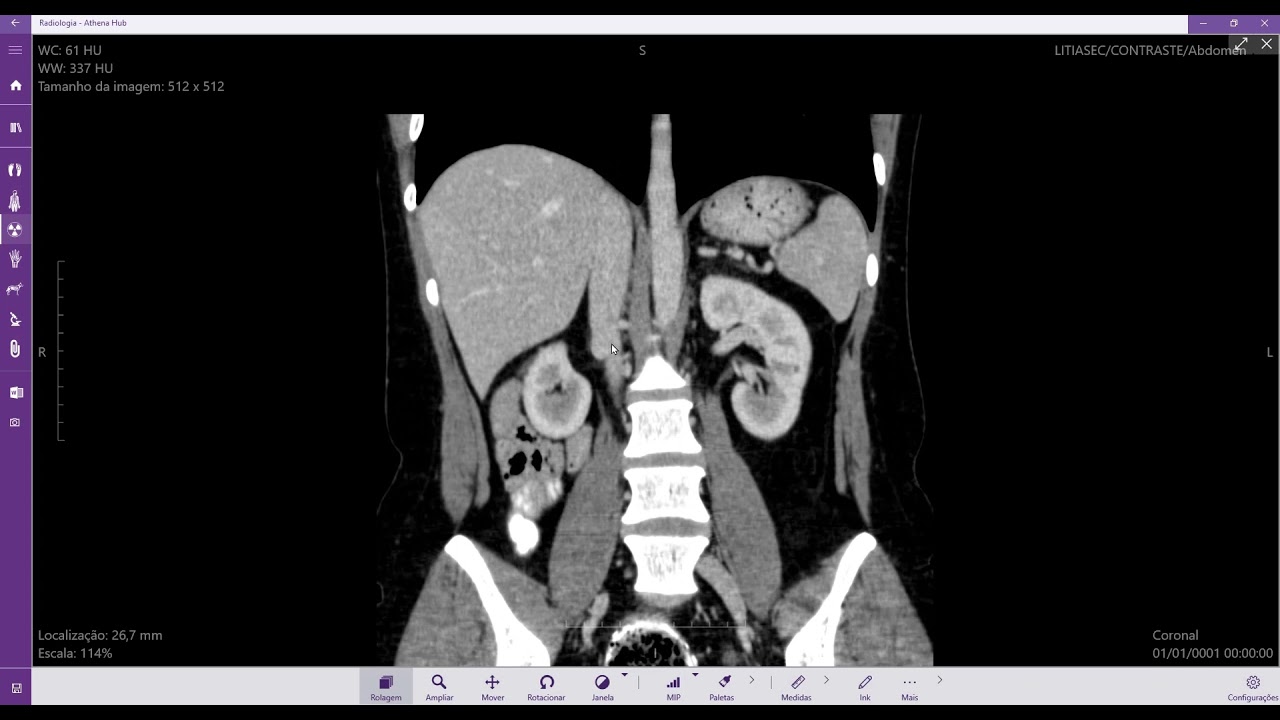

A veia cava inferior é um vaso sanguíneo longo e estreito que se estende da pelve até o tórax. Ela é formada pela junção das veias ilíacas comuns direita e esquerda, na pelve. Na pelve, a veia cava inferior recebe o sangue da veia ilíaca interna e da veia ilíaca externa. No tórax, a veia cava inferior recebe o sangue da veia renal direita e esquerda, da veia frénica inferior e da veia suprarenal esquerda.

As principais patologias que podem afetar a veia cava inferior são:

- Trombose venosa profunda (TVP): é uma condição na qual um coágulo de sangue se forma em uma veia profunda, geralmente nas pernas. A TVP pode causar dor, inchaço e vermelhidão na perna afetada.

- Insuficiência venosa crônica (IVC): é uma condição na qual as veias não conseguem bombear o sangue de volta ao coração de forma eficaz. A IVC pode causar dor, inchaço e úlceras nas pernas.

- Tumores venosos: são tumores que se desenvolvem nas veias. Os tumores venosos são geralmente benignos, mas podem causar sintomas como dor, inchaço e obstrução do fluxo sanguíneo.

A veia cava inferior é um vaso sanguíneo importante que transporta o sangue do tronco inferior do corpo para o coração. A compreensão da anatomia e da função da veia cava inferior é essencial para o diagnóstico e o tratamento de doenças que podem afetar esse vaso sanguíneo.